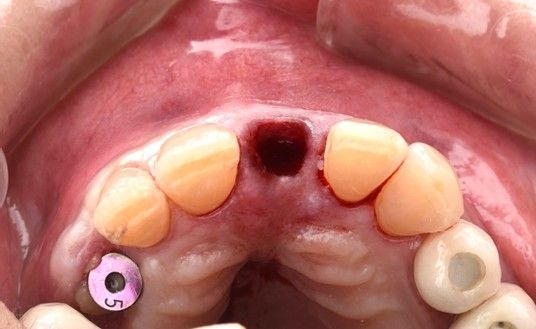

Bajo anestesia local mediante articaína al 4 % con epinefrina 1:100.000 (Ultracain®), se realizó una exodoncia atraumática utilizando mini luxadores, con el objetivo de preservar al máximo los tejidos duros y blandos (Figura 3). Tras la extracción, el alveolo fue cuidadosamente legrado y desinfectado mediante irrigación secuencial con peróxido de hidrógeno al 1,5%, clorhexidina al 0,20 % y suero salino estéril.